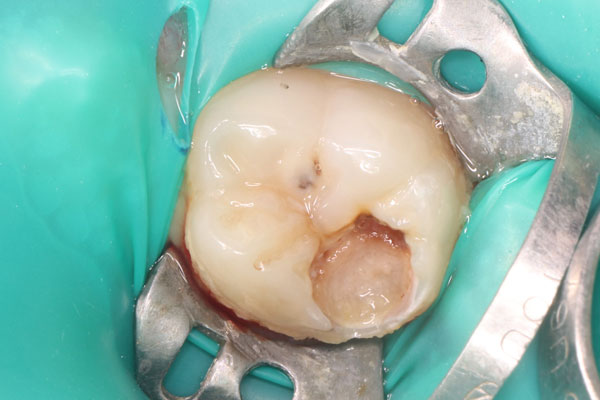

Наши работы

Показания для наркоза детям:

- Предстоящий большой объем стоматологического вмешательства;